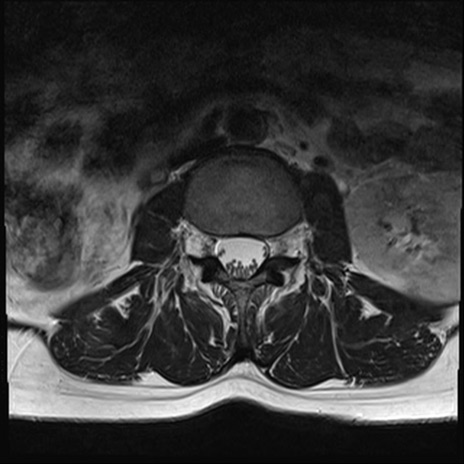

【整形】TIPS症例4 腰椎MRI T2WI(横断像)

腰椎MRI

横断像と矢状断像